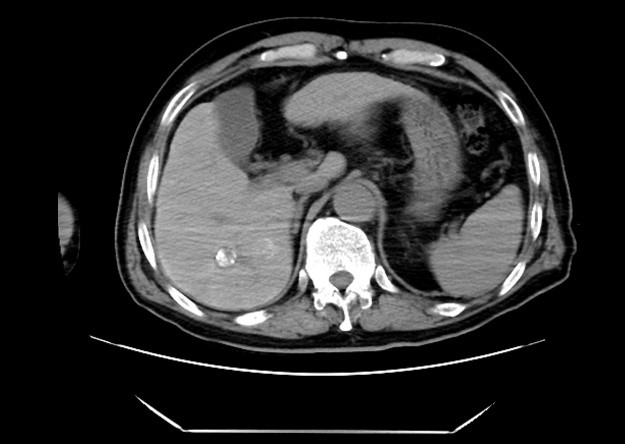

出院1个月后,患者门诊复查MRI见肝脏病灶活性消失,肿瘤已经被消除干净,术后甲胎蛋白也下降至正常水平,已经达到临床根治疗效。患者十分开心,对程医生及独墅湖医院介入与血管外科为他消除了病痛表达了感谢。

(术后1个月复查MRI见肝脏病灶无活性)